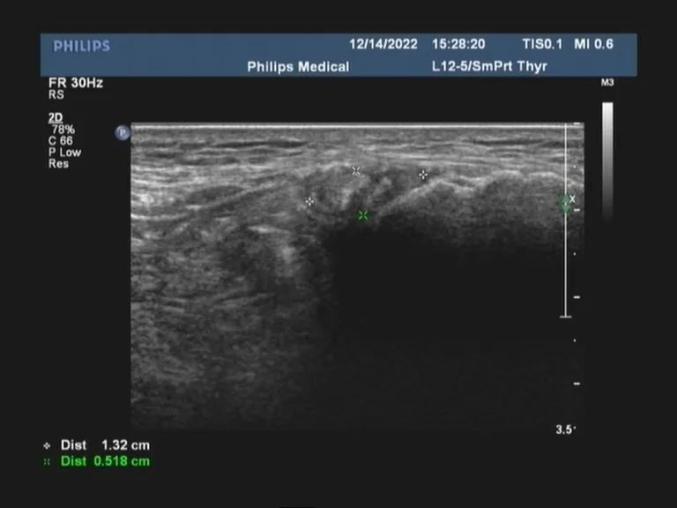

关节超声显示痛风石沉积